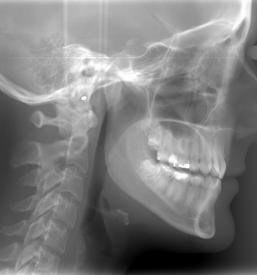

Svojim pacientom nudimo dober RTG zob v Ljubljani, center, kjer se nahaja naša ordinacija. Nudimo vam varno in natančno slikanje zob, ki je odločilnega pomena za nadaljnjo zdravljenje in zobozdravstveno obravnavo.

Pri svojem delu uporabljamo le najboljšo opremo, ki zagotavlja, da je RTG zob, ki ga opravljamo v Ljubljani, center, povsem varen, učinkovit, rezultati pa hitri in nazorni.

Rezultate, ki jih prinaša naš dober RTG zob v Ljubljani interpretirajo strokovnjaki in na podlagi slike določijo diagnozo in nadaljnjo zdravljenje, ki je potrebno za doseganje optimalnega stanja.